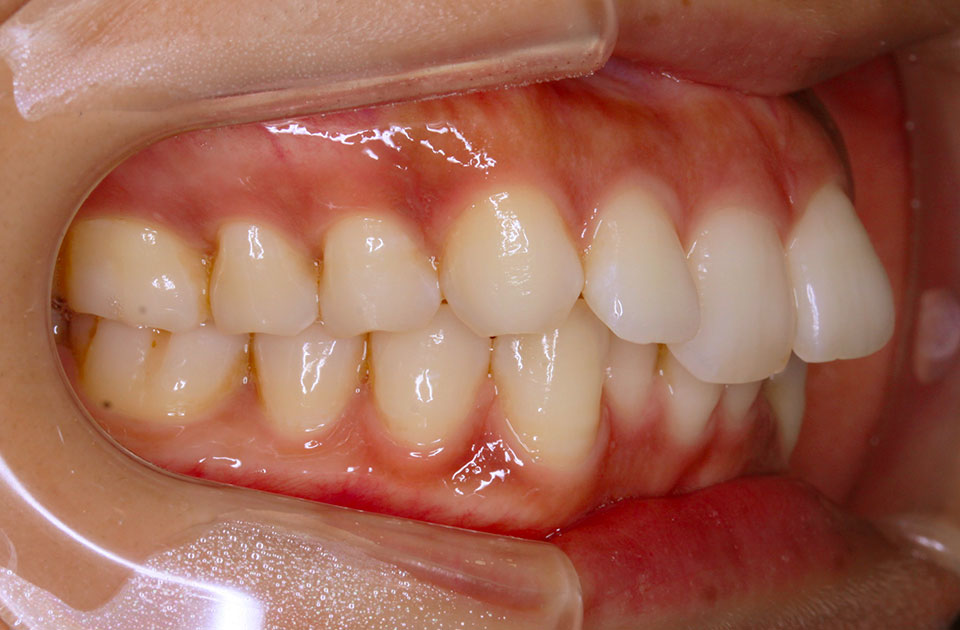

矯正前 左側

矯正後 左側